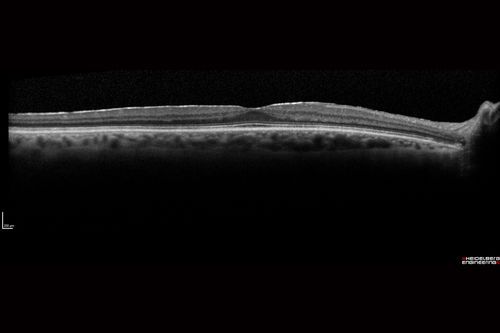

Pigmented Paravenous Retinochoroidal Atrophy - Left Eye

70 year old woman lost vision OS 20 years ago.